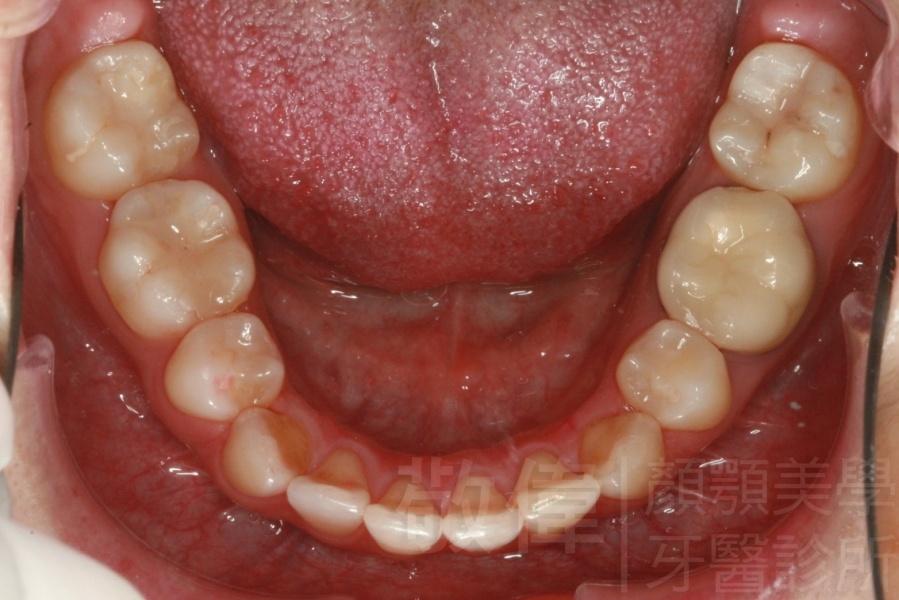

齒顏矯正/上顎暴牙且牙齒極度混亂

矯正前-上   矯正前-下

<個案說明>

上顎暴牙且牙齒極度混亂,經由矯正之後,臉型大幅度改善,牙齒的排列更加的整齊健康。相較於之前眼神充滿精神,自信心展現無遺。